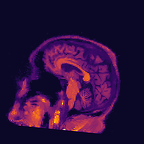

Multi-modality (or multi-channel) imaging is becoming increasingly important and more widely available, e.g. hyperspectral imaging in remote sensing, spectral CT in material sciences as well as multi-contrast MRI and PET-MR in medicine. Research in the last decades resulted in a plethora of mathematical methods to combine data from several modalities. State-of-the-art methods, often formulated as variational regularization, have shown to significantly improve image reconstruction both quantitatively and qualitatively. Almost all of these models rely on the assumption that the modalities are perfectly registered, which is not the case in most real world applications. We propose a variational framework which jointly performs reconstruction and registration, thereby overcoming this hurdle. Numerical results on simulated and real data show the potential of the proposed strategy for various applications in multi-contrast MRI, PET-MR, and hyperspectral imaging: typical misalignments between modalities such as rotations, translations, zooms can be effectively corrected during the reconstruction process. Therefore the proposed framework allows the robust exploitation of shared information across multiple modalities under real conditions.

翻译:多模式(或多通道)成像越来越重要,而且越来越普及,例如遥感中的超光谱成像、材料科学中的光谱CT以及医学中的多调MRI和PET-MR等,过去几十年的研究产生了大量数学方法,将多种模式的数据结合起来。通常作为变异性正规化的先进方法表明,在数量和质量上都大大改进了图像重建。几乎所有这些模型都基于这样一种假设,即模式已经完全登记,而在大多数现实世界应用中情况并非如此。我们提议了一个变通框架,共同进行重建和登记,从而克服这一障碍。模拟和实际数据的数字结果显示,拟议的多调MRI、PET-MR和超光谱成像的各种应用战略具有潜力:在重建过程中可以有效地纠正诸如轮换、翻译、缩影等模式之间的典型的不匹配。因此,拟议的框架允许在现实条件下,在多种模式中大力利用共享的信息。